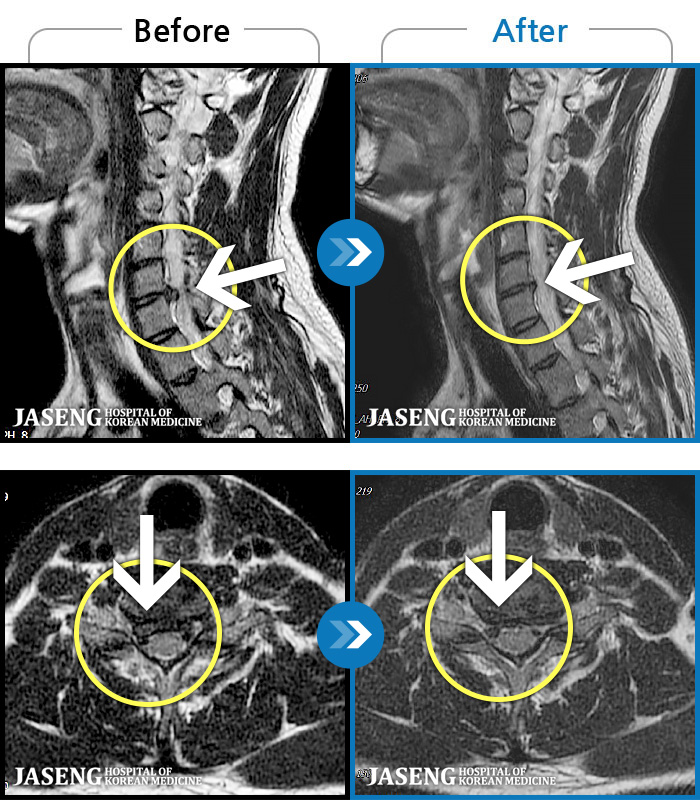

MRI ġ

1,245 MRI ũ ʸ Ȯϼ.